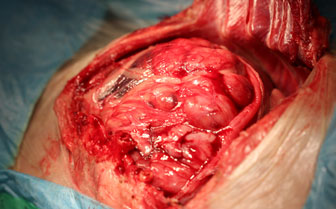

飼い主様からの希望により、手術にて肝臓に発生した腫瘍の摘出手術を行いました。これくらい大きくなるとかなり危険な手術になることが予想されます。

開腹した時の写真です。巨大な肝臓腫瘍が確認されました。

意外にスムーズに肝臓の腫瘍が摘出できました。出血もほとんどありません。